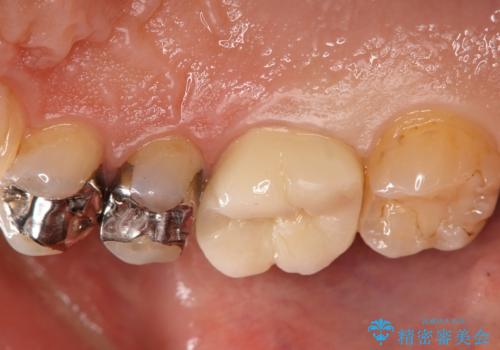

銀歯をセラミックに変えたい

- 銀歯のセラミックへのやり替えをご希望で来院されました。

銀歯が入ってる歯は複数箇所ありましたが、咬合力がより強く破折リスクが高い奥歯から治療を開始してます。

奥歯の噛み合わせが強く、治療後にセラミックが割れるリスクがあった為マウスピースの装着をして頂いてます。

他の銀歯については患者様のご希望のタイミングで治療していく予定です。